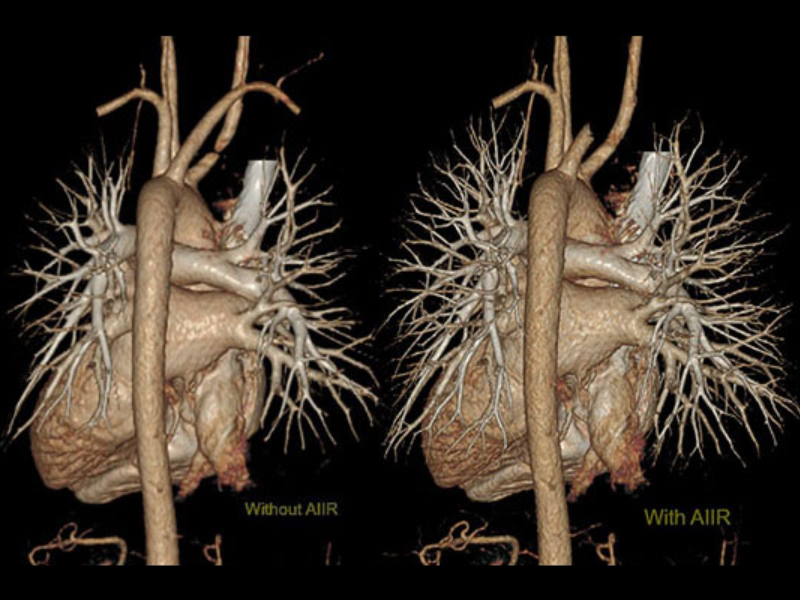

Masterful Image Reconstruction

uAI AI-IR significantly reduces image noise and artifacts, while at the same time greatly improves low contrast detectability and spatial resolution. Enhanced spatial resolution can also be achieved through the combination of the 0.5 mm collimation and 1024*1024 reconstruction matrix to help reveal the smallest of detailed for the most challenging examinations.